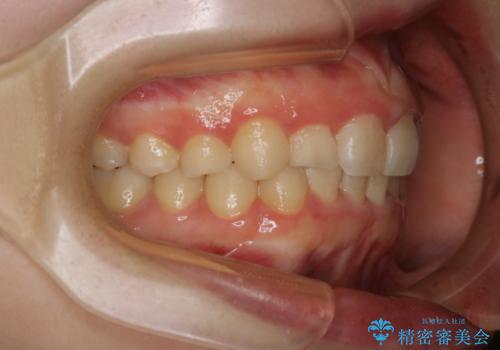

前歯のがたつきとディープバイト:インビザライン治療

- 前歯のがたつきと、噛み合わせが深いことを気にされてご相談にいらした方です。

インビザラインにて治療を行いました。

一般的に、歯冠(歯の長さ)が短い方はインビザライン治療に時間がかかりやすい傾向にあります。

歯の移動量に対して大きなブラックトライアングルもできることなく綺麗に並べることができ、大変喜んでいただけました。